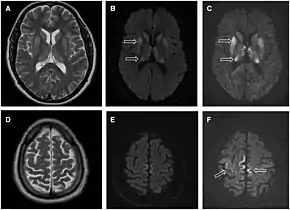

MRI of iCJD because of growth hormone

The defective protein can be transmitted by contaminated harvested human brain products, corneal grafts,[23] dural grafts,[24] or electrode[25] implants and human growth hormone.[26]

Brain MRI is the most useful imaging modality for changes related to CJD. Of the MRI sequences, diffuse-weighted imaging sequences are most sensitive.[46] Characteristic findings are as follows:

dwMRI, FDG PET and post mortem histology from a patient who presented with sCJD aged 66

• Focal or diffuse diffusion-restriction involving the cerebral cortex and/or basal ganglia. In about 24% of cases DWI shows only cortical hyperintensity; in 68%, cortical and subcortical abnormalities; and in 5%, only subcortical anomalies.[47] The most iconic and striking cortical abnormality has been called "cortical ribboning" or "cortical ribbon sign" due to hyperintensities resembling ribbons appearing in the cortex on MRI.[48] The involvement of the thalamus can be found in sCJD, is even stronger and constant in vCJD.[49]

• Varying degree of symmetric T2 hyperintense signal changes in the basal ganglia (i.e., caudate and putamen), and to a lesser extent globus pallidus and occipital cortex.[44]

Brain FDG PET-CT tends to be markedly abnormal, and is increasingly used in the investigation of dementias.

• Patients with CJD will normally have hypometabolism on FDG PET.[50]